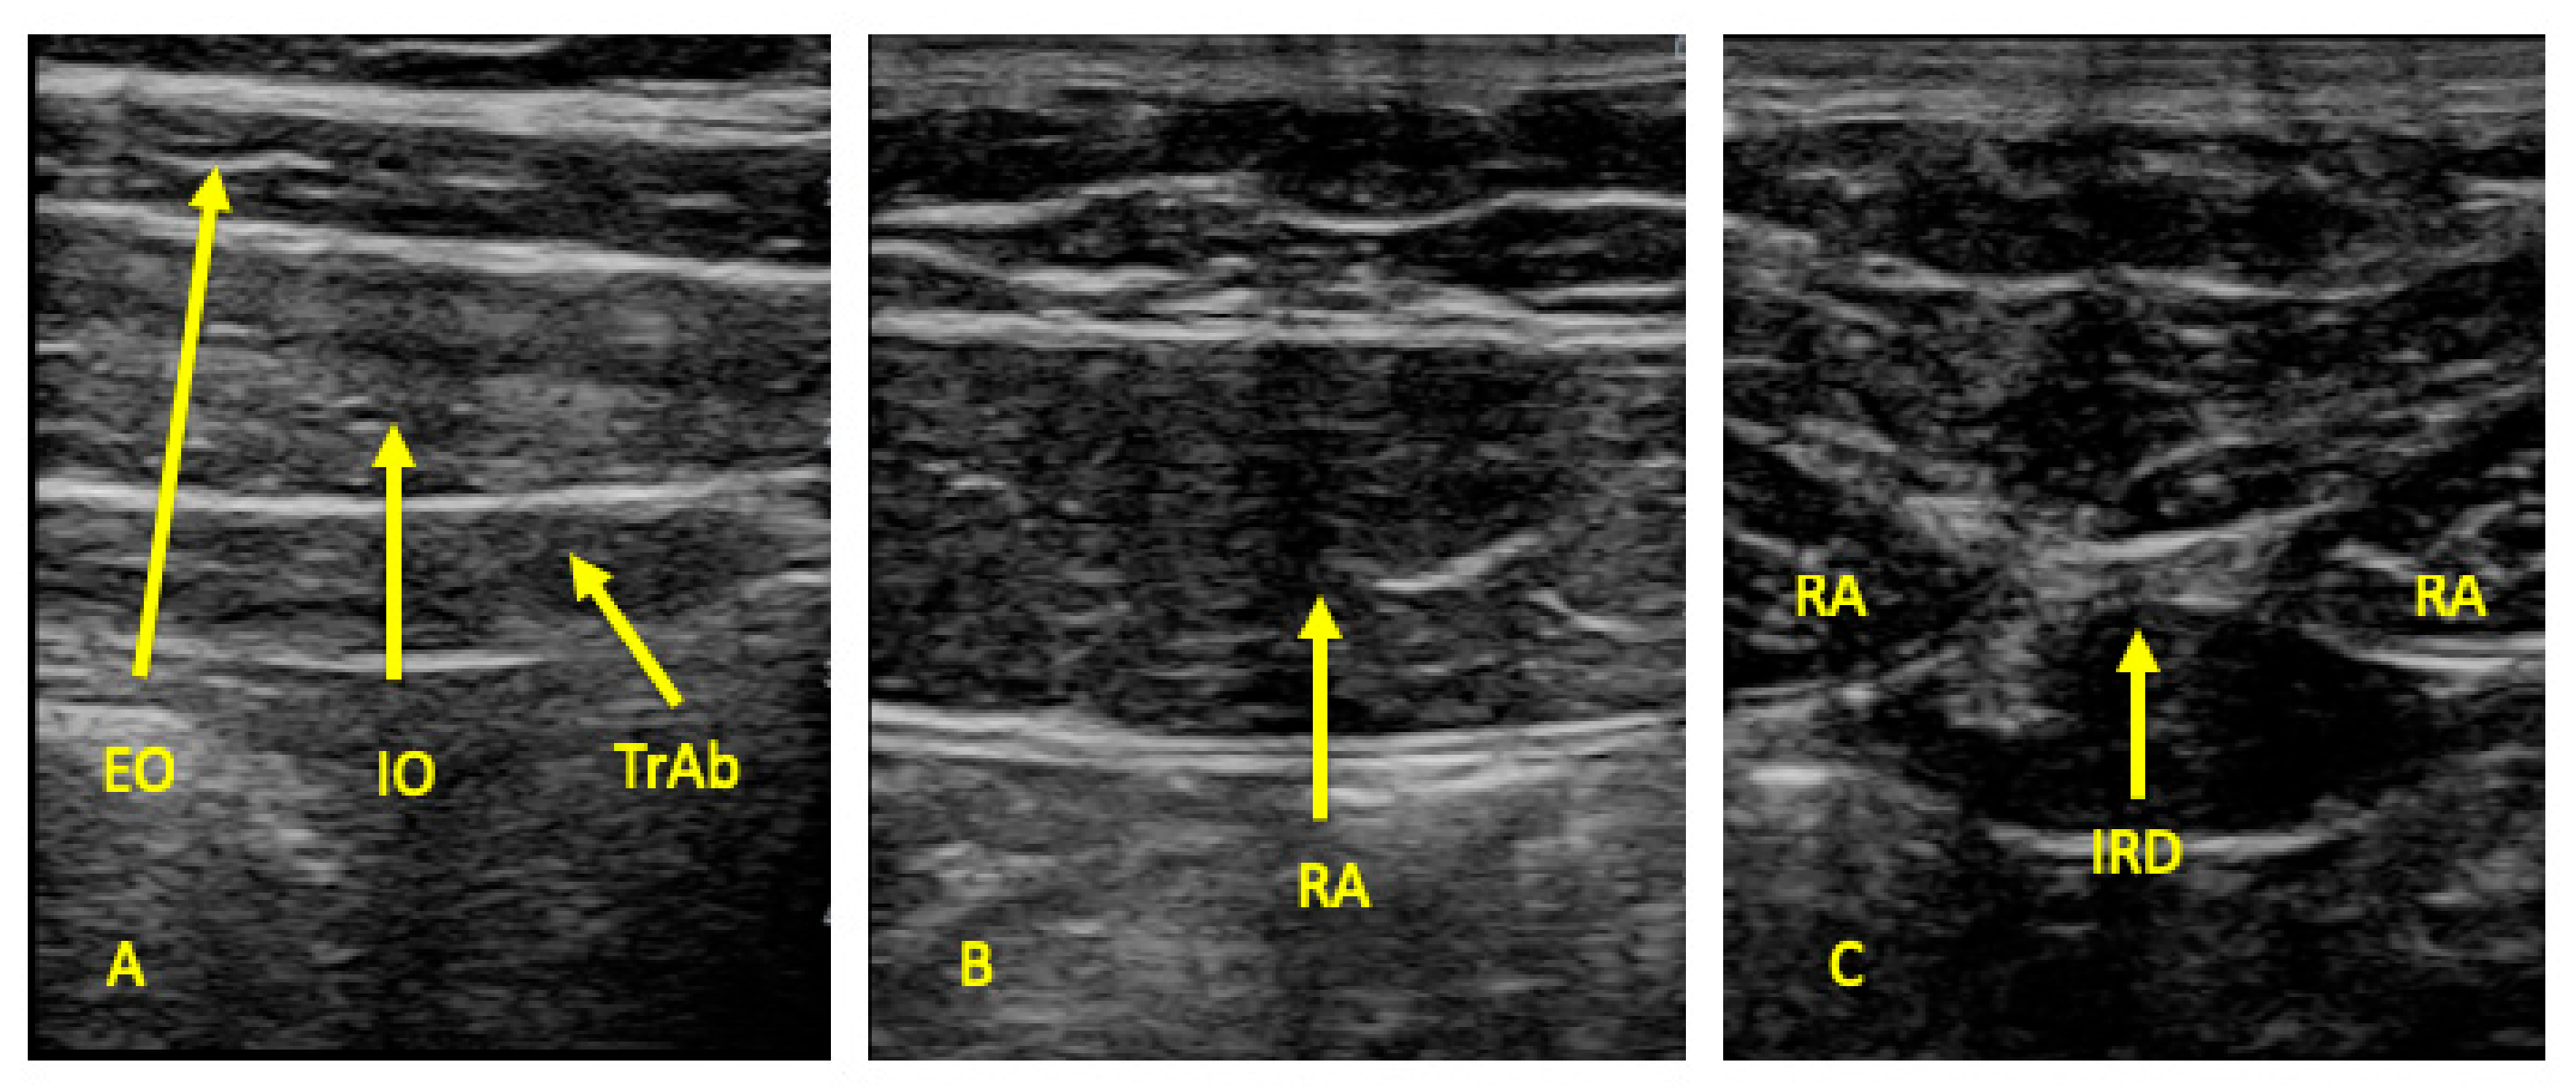

2.4. Outcome Measures